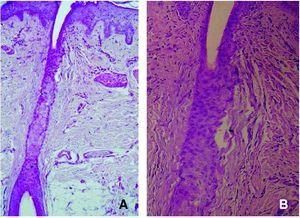

El cuadro histopatológico descrito originalmente por Kossard y confirmado en estudios posteriores, consistió en la presencia de un infiltrado perifolicular liquenoide a la altura del istmo e infundíbulo, con fibrosis perifolicular en capas de cebolla y fibrosis lamelar a la misma altura que el infiltrado inflamatorio1,2. Estas manifestaciones histopatológicas, demostradas en las 16 pacientes de la serie de Kossard, fueron indistinguibles de los cambios histopatológicos de los casos de LPP multifocal. Sin embargo, en la serie clínicopatológica de Poblet et al se describieron cambios dermatopatológicos que pueden permitir el diagnóstico diferencial entre ambas entidades7 (fig. 4 y tabla 3).

Figura 4. Imagen histopatológica de la alopecia frontal fibrosante en la que se observa un infiltrado inflamatorio perifolicular leve (hematoxilina-eosina, ×40) (A), con fibrosis lamelar alrededor del istmo e infundíbulo folicular (hematoxilina-eosina, ×100) (B).